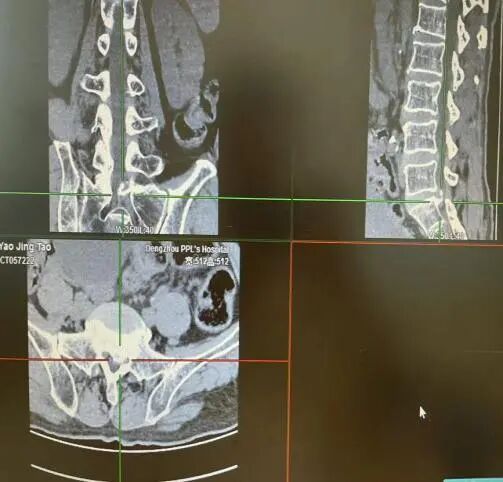

冀先生,73岁,腰疼5年伴双下肢无力2月余,行走200米后症状加重,间歇性跛行。入院完善检查诊断为:腰4-5椎间盘突出伴椎管狭窄。在全麻下行腰4—5椎管狭窄单侧入路双侧减压(UBE-ULBD)术后间歇性跛行缓解,下肢无力症状好转。

图片

病例二:

刘女士,73岁,左下肢疼痛伴间歇性跛行半年。经系统保守治疗后无缓解,入院完善检查诊断为:腰3-4椎间盘突出伴椎管狭窄。在全麻下行腰3-4椎管狭窄单侧入路双侧减压(UBE-ULBD)术后下肢疼痛缓解,无力症状缓解。